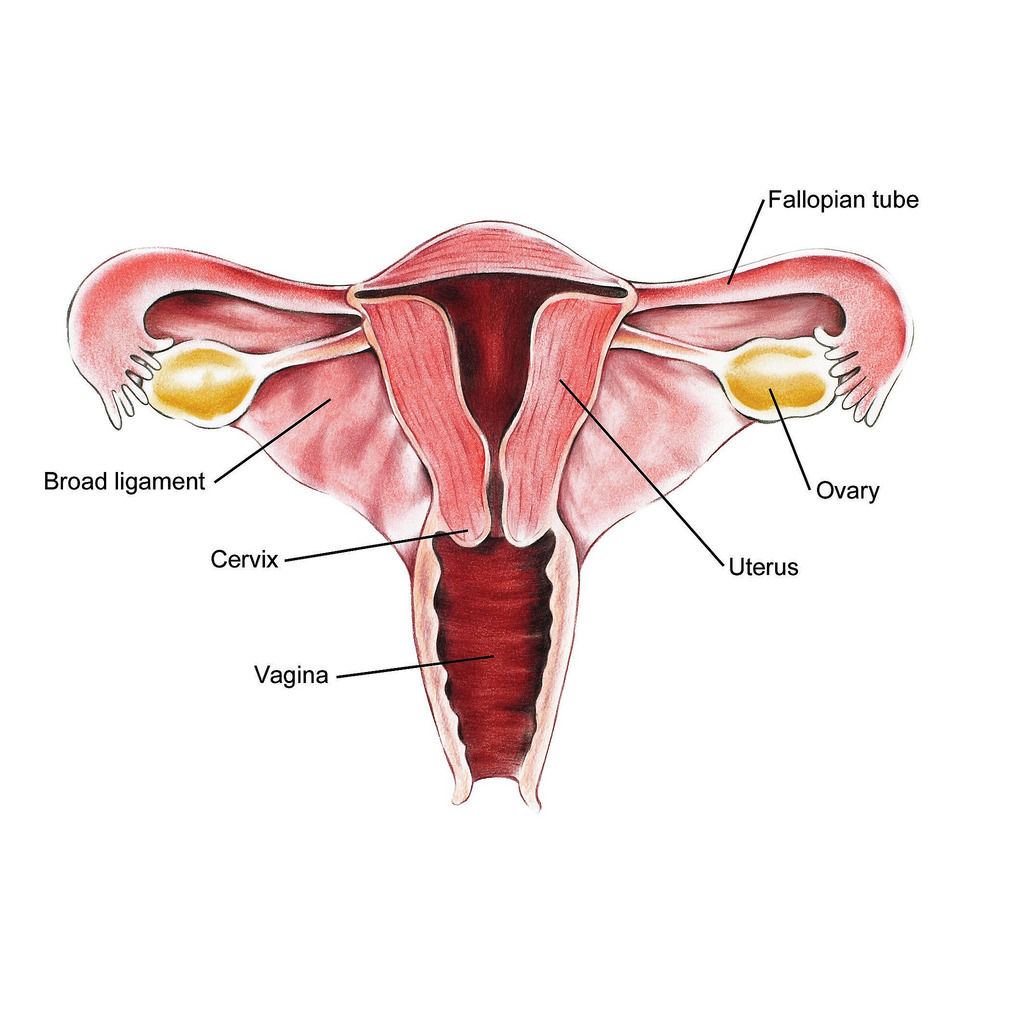

اندومتریوز؛ آندومتر بافتی است که داخل رحم را می پوشاند. اندومتریوز وضعیتی است که در آن بافتی مشابه به بافت آندومتر در خارج از قسمت رحم یافت می شود. در ناحیه لگن و شکم تحتانی (شکم) و به ندرت در سایر نواحی بدن «به دام افتاده» است. در حال حاضر مشخص نیست که چه چیزی باعث آندومتریوز می شود. عوامل متعددی وجود دارد که احتمالاً دلایل ژنتیکی، ایمونولوژیکی و هورمونی را شامل می شود.

این بیماری زمانی اتفاق میافتد که بافت مشابه با بافت داخلی رحم (آندومتر) در جایی خارج از رحم رشد میکند، معمولاً در تخمدانها، لولههای فالوپ یا سایر اندامهای لگنی. علائم آندومتریوز میتواند شامل دردهای شدید قاعدگی، درد در حین رابطه جنسی، مشکلات باروری و خونریزی غیر طبیعی باشد. با این حال، بسیاری از زنان مبتلا به آندومتریوز ممکن است بدون علائم جدی یا فقط علائم خفیف داشته باشند، که این ممکن است تشخیص بیماری را دشوار کند.

اندومتریوز یک بیماری زنان است که در آن بافتی مشابه به بافت داخلی رحم (اندومتر) در خارج از رحم رشد میکند. این بیماری میتواند به شدت دردناک باشد و مشکلاتی چون ناباروری، دردهای مزمن لگنی، و اختلالات قاعدگی را ایجاد کند. تشخیص زودهنگام اندومتریوز اهمیت زیادی دارد زیرا میتواند به مدیریت مؤثرتر علائم و بهبود کیفیت زندگی بیماران کمک کند. یکی از روشهای رایج و غیرتهاجمی برای تشخیص اندومتریوز استفاده از سونوگرافی است که به ویژه در شناسایی برخی از ویژگیهای این بیماری بسیار مؤثر است.

آندومتر پوشش داخلی رحم (رحم) است. این بافت به طور معمول در طول چرخه قاعدگی مراحل رشد و ریزش را طی می کند. آندومتریوز زمانی رخ می دهد که آندومتر خارج از محل معمول قرار داشته باشد. اندومتریوز ممکن است در تخمدان ها، لوله های فالوپ، واژن یا سایر قسمت های رحم رخ دهد. به ندرت ممکن است اندومتریوز در شکم و ریه ها رخ دهد.

اندومتریوز یک بیماری خوش خیم زنانه در آندومتر است، بافتی که در داخل رحم قرار دارد و به طور مشخص مسئول قاعدگی است. آندومتر پوشش داخلی رحم است.

آندومتریوز با وجود بافت آندومتر در خارج از رحم، یعنی روی تخمدانها، لولههای فالوپ، رباطهای ساکرال رحم (رباطهایی که از رحم حمایت میکنند)، صفاق، مثانه، روده و به ندرت ریهها و حتی مغز مشخص میشود.